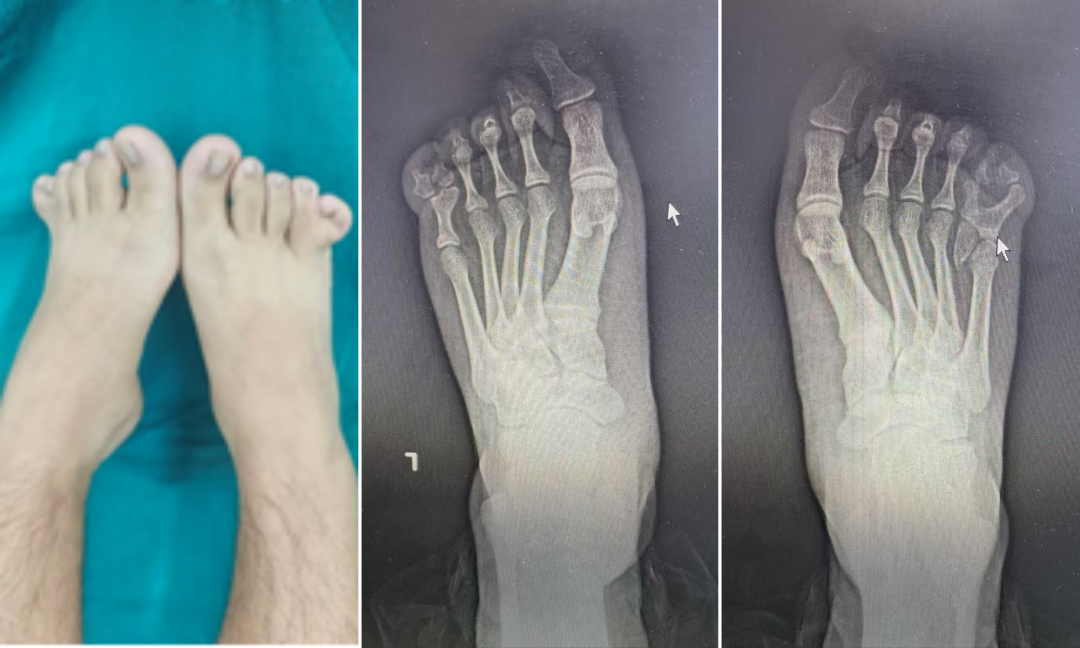

对于每一个孩子来说,拥有一双健康的双脚,能无拘无束地奔跑,是成长中最珍贵的权利。但先天性足趾多趾、并趾畸形,却让不少孩子从小背负身体与心理的双重压力,不仅影响足部外观和穿鞋行走,更可能在成长中埋下自卑的种子。近日,北华大学附属医院手足外科团队成功完成1例双足足趾多趾并趾畸形矫正手术。 患者为青少年,自幼双足存在多趾合并并趾畸形,脚趾数量异常、趾体粘连,不仅外观与常人不同,穿鞋磨脚、行走受力不均,长期还可能影响步态与足部发育。随着年龄增长,孩子逐渐在意他人目光,不愿露出双脚。为了让孩子彻底摆脱困扰,家人多方了解后,专程来到我院寻求专业治疗。 患者入院后进行相关检查,结合影像学资料,清晰判断骨骼、关节、肌腱、神经血管走向,精准分型、精细规划。考虑到患者年轻,对外观与功能要求高,手足外科团队为他制定个体化矫形方案:精准切除多余足趾,精细分离并连趾体,重建趾蹼,修复重建软组织与皮肤,兼顾足部功能与长期发育,尽可能让切口隐蔽、愈合平整、术后不留明显痕迹。 矫形手术是一项精细的“手工活”,需要在麻醉下由经验丰富的医生操作。主要包括两个核心步骤: 1.切除多趾 医生根据X光片和外观,准确判断哪一个是需要切除的“多趾”。保留皮肤和软组织,精准切除多余的骨骼,同时修复足部的韧带和肌腱,确保保留的脚趾稳定、有力,排列整齐。 2.分离并趾 医生在并趾之间设计皮瓣,重建趾蹼,而不是直切口。这样可以避免术后疤痕直线挛缩,导致脚趾再次并在一起。如果并趾分得太开,中间皮肤不够,就需要从腹股沟取一小块薄薄的皮肤进行植皮,以保证伤口完美愈合。 手术当日,医院第一梯队红医名家、手足外科主任赵维彦带科室主治医师孙汝鑫在麻醉科与护理团队的密切配合下,顺利完成手术。赵维彦团队以极高的精细度完成矫形与修复,最大限度保留正常组织,确保患者术后行走、运动功能不受影响。 术后,男孩恢复良好,已经可以正常穿鞋、正常走路、自由活动,再也不用刻意隐藏双脚。困扰多年的烦恼彻底解决,孩子脸上重新露出轻松、自信的笑容,勇敢追求自己的梦想。一双脚的改变,真的可以照亮一整个青春。 手足外科主任赵维彦特别提醒:多趾、并趾是儿童/青少年常见先天性足部畸形,越早接受规范治疗,效果越好、恢复越快、外形越自然。早期干预不仅能改善功能、避免受力异常,更能保护孩子心理健康,让孩子在成长中自信、阳光、不留阴影。 本文通讯员 手足外科 王琦 本文专家 供稿丨手足外科 编辑丨吴志成 初审丨赵维彦 复审丨尹莉 终审丨王华